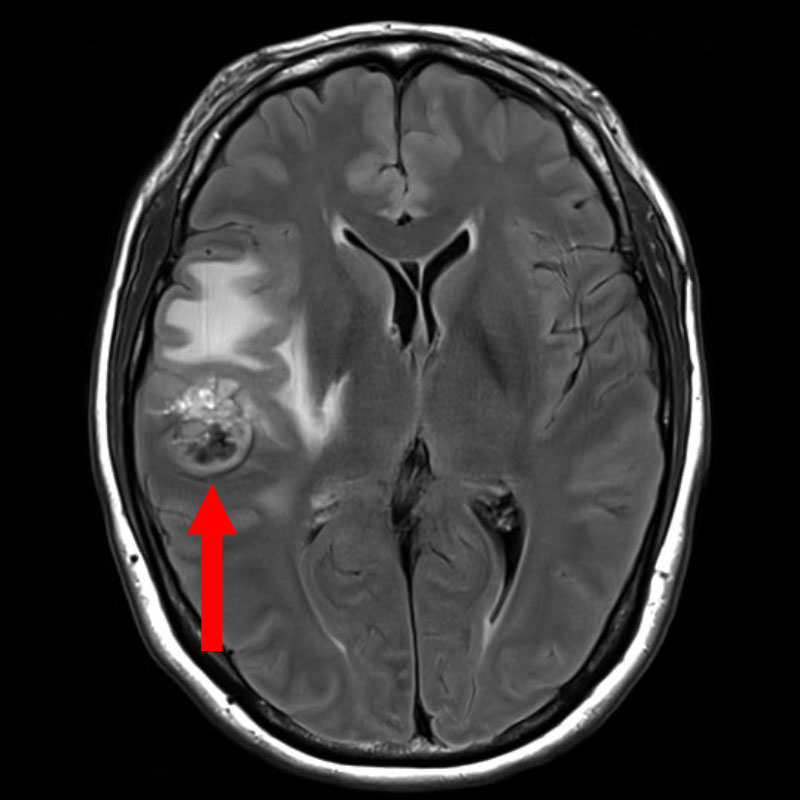

手術前1

手術前2